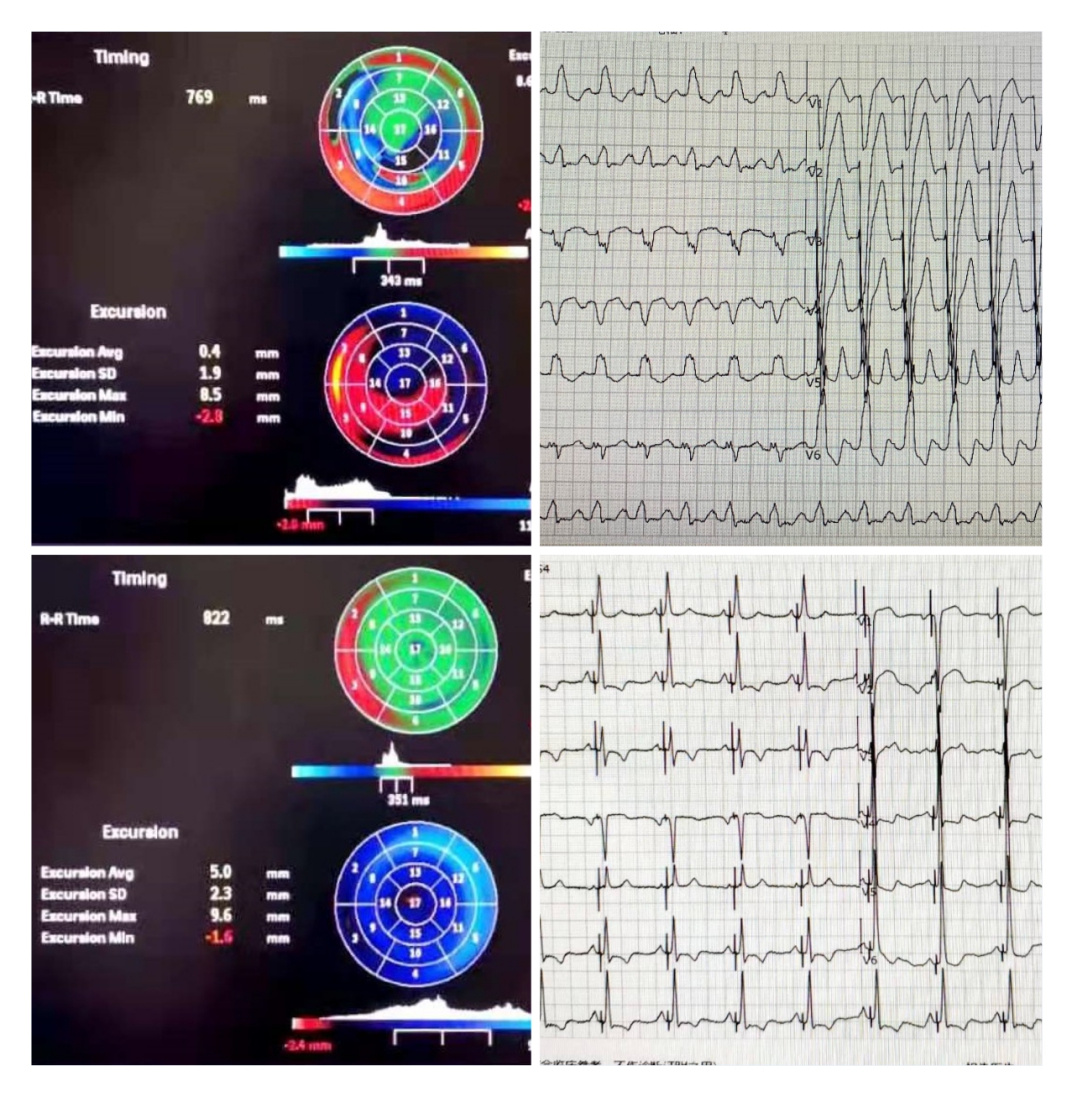

手术全程耗时1个多小时。术后进行心脏彩超检查结果显示左室收缩同步性显著改善,希浦系统起搏完美实现了心脏电学及机械再同步!

(上图上面部分分别为患者自身完左心电图以及完左状态下的牛眼图;下面部分为希浦系统起搏后的心电图以及对应状态下的牛眼图)